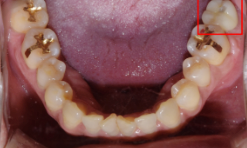

After(후)

사진을 보시면 임플란트가 안정적으로 자리 잡은 것을 확인해 보실 수 있습니다.

Before(전) : After(후)

이분은 SCRP 크라운 보철물로 치료를 진행하였습니다.

SCRP 보철물은 사후관리가 용이하다는 장점을 가지고 있습니다. 우측 사진을 보시면 치료받은 치아에 동그라미를 확인해 보실 수 있는데요. 이게 작은 구멍입니다.

이 구멍을 통해 나사 조임을 조절하여 언제든지 보철물이 탈부착이 가능하기에, 보철물을 위생적으로 관리할 수 있습니다.